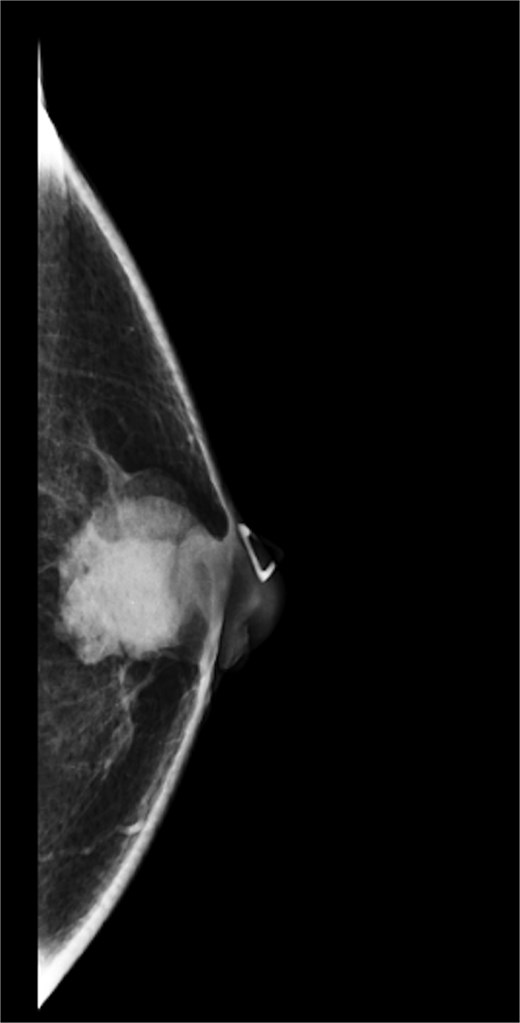

A 63-year-old male with a past medical history of heavy daily tobacco use, COPD, and a left breast leiomyoma diagnosed in 2018 presented to a general surgeon with a nonhealing left breast abscess. The patient had a persistent 3 cm retroareolar mass despite multiple incision and drainage procedures. On exam, the left axillary lymph nodes were unremarkable and the nipple, while not inverted, was chronically distorted, indurated, and inflamed. The persisting mass and inflammation were initially concerning for inflammatory breast cancer. Superficial biopsy by both a dermatologist and general surgeon were equivocal. Diagnostic mammogram and targeted left breast ultrasound revealed a retroareolar 3.3 × 3.6 × 2.7 cm heterogenous mass, corresponding to the area of palpable concern (Figs 1 and 2).

Diagnostic mammogram of left breast showing heterogenous retroareolar mass – first view.